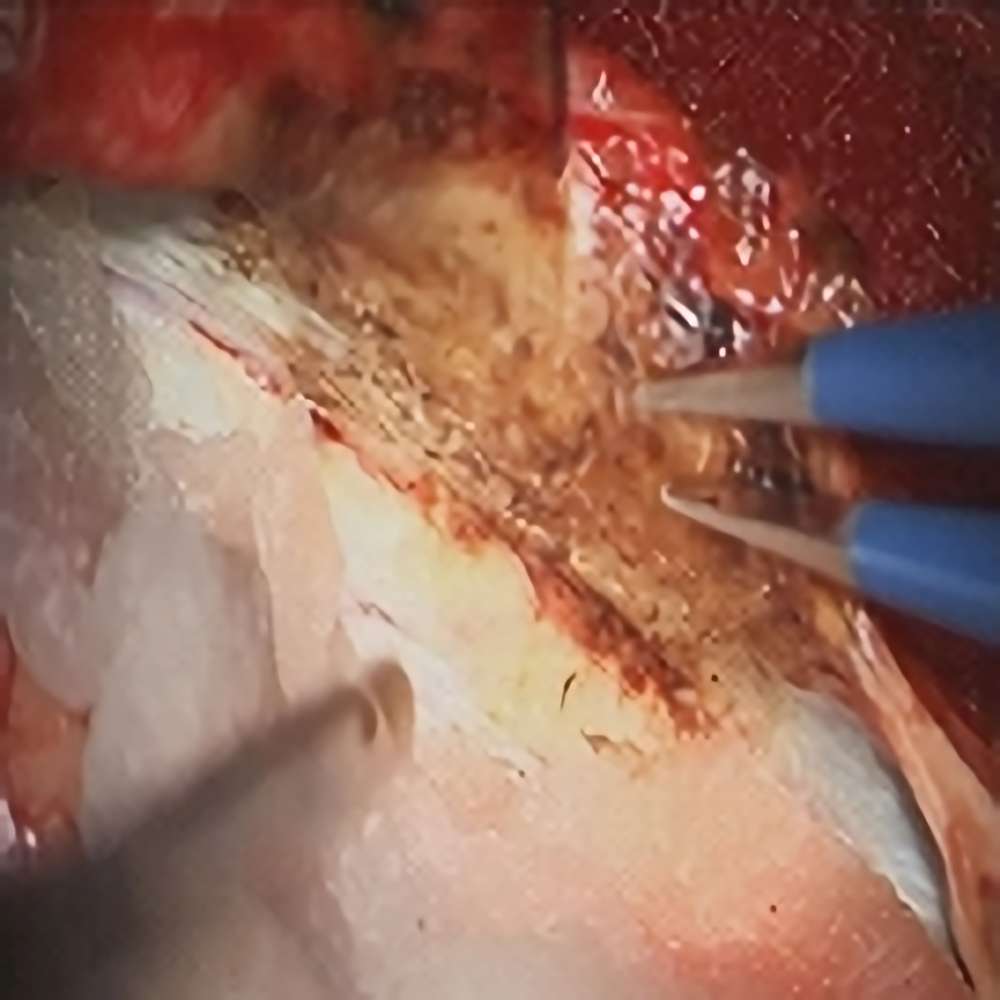

錐体斜台部髄膜腫

頭蓋内腫瘍摘出術

No.’22_88 摘出 前

No.’22_88  摘出 中

No.’22_88 摘出 後